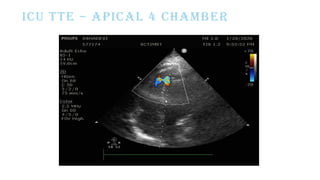

ECHO-

5mm Apical VSD L-R

shunt gradient-

63mmHg

RWMA+

ICU TTE – APICAL 4 CHAMBER